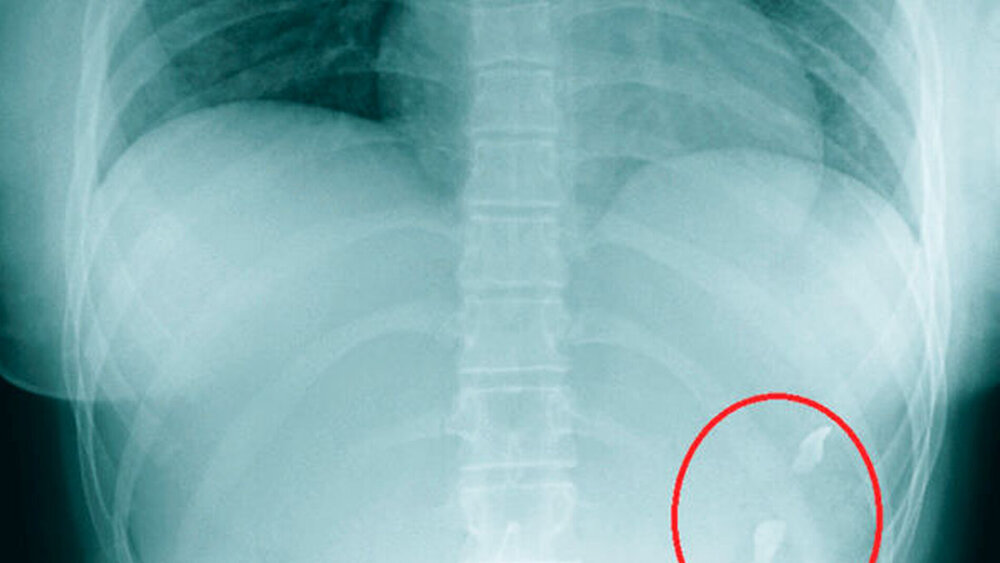

Klinisch konnten extraoral eine Riss-Quetsch-Wunde der Unterlippe sowie Schürfwunden am Kinn festgestellt werden. Intraoral war die vollständige Avulsion der Zähne 12, 11 und 21 sichtbar. Das im Rahmen des Schockraummanagements durchgeführte Thorax-Röntgen offenbarte drei röntgendichte Strukturen in Projektion auf den linken Oberbauch (Abbildung 1), so dass der Verdacht auf eine Ingestion der drei avulsierten Zähne mit Lage im Magenlumen geäußert wurde.